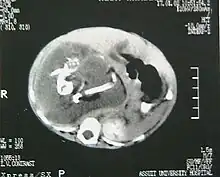

A computed tomography scan of the same patient's abdomen pre-operation reveals a large retroperitoneal soft-tissue mass. There are long hyperdense opacities that resemble fetal bones.